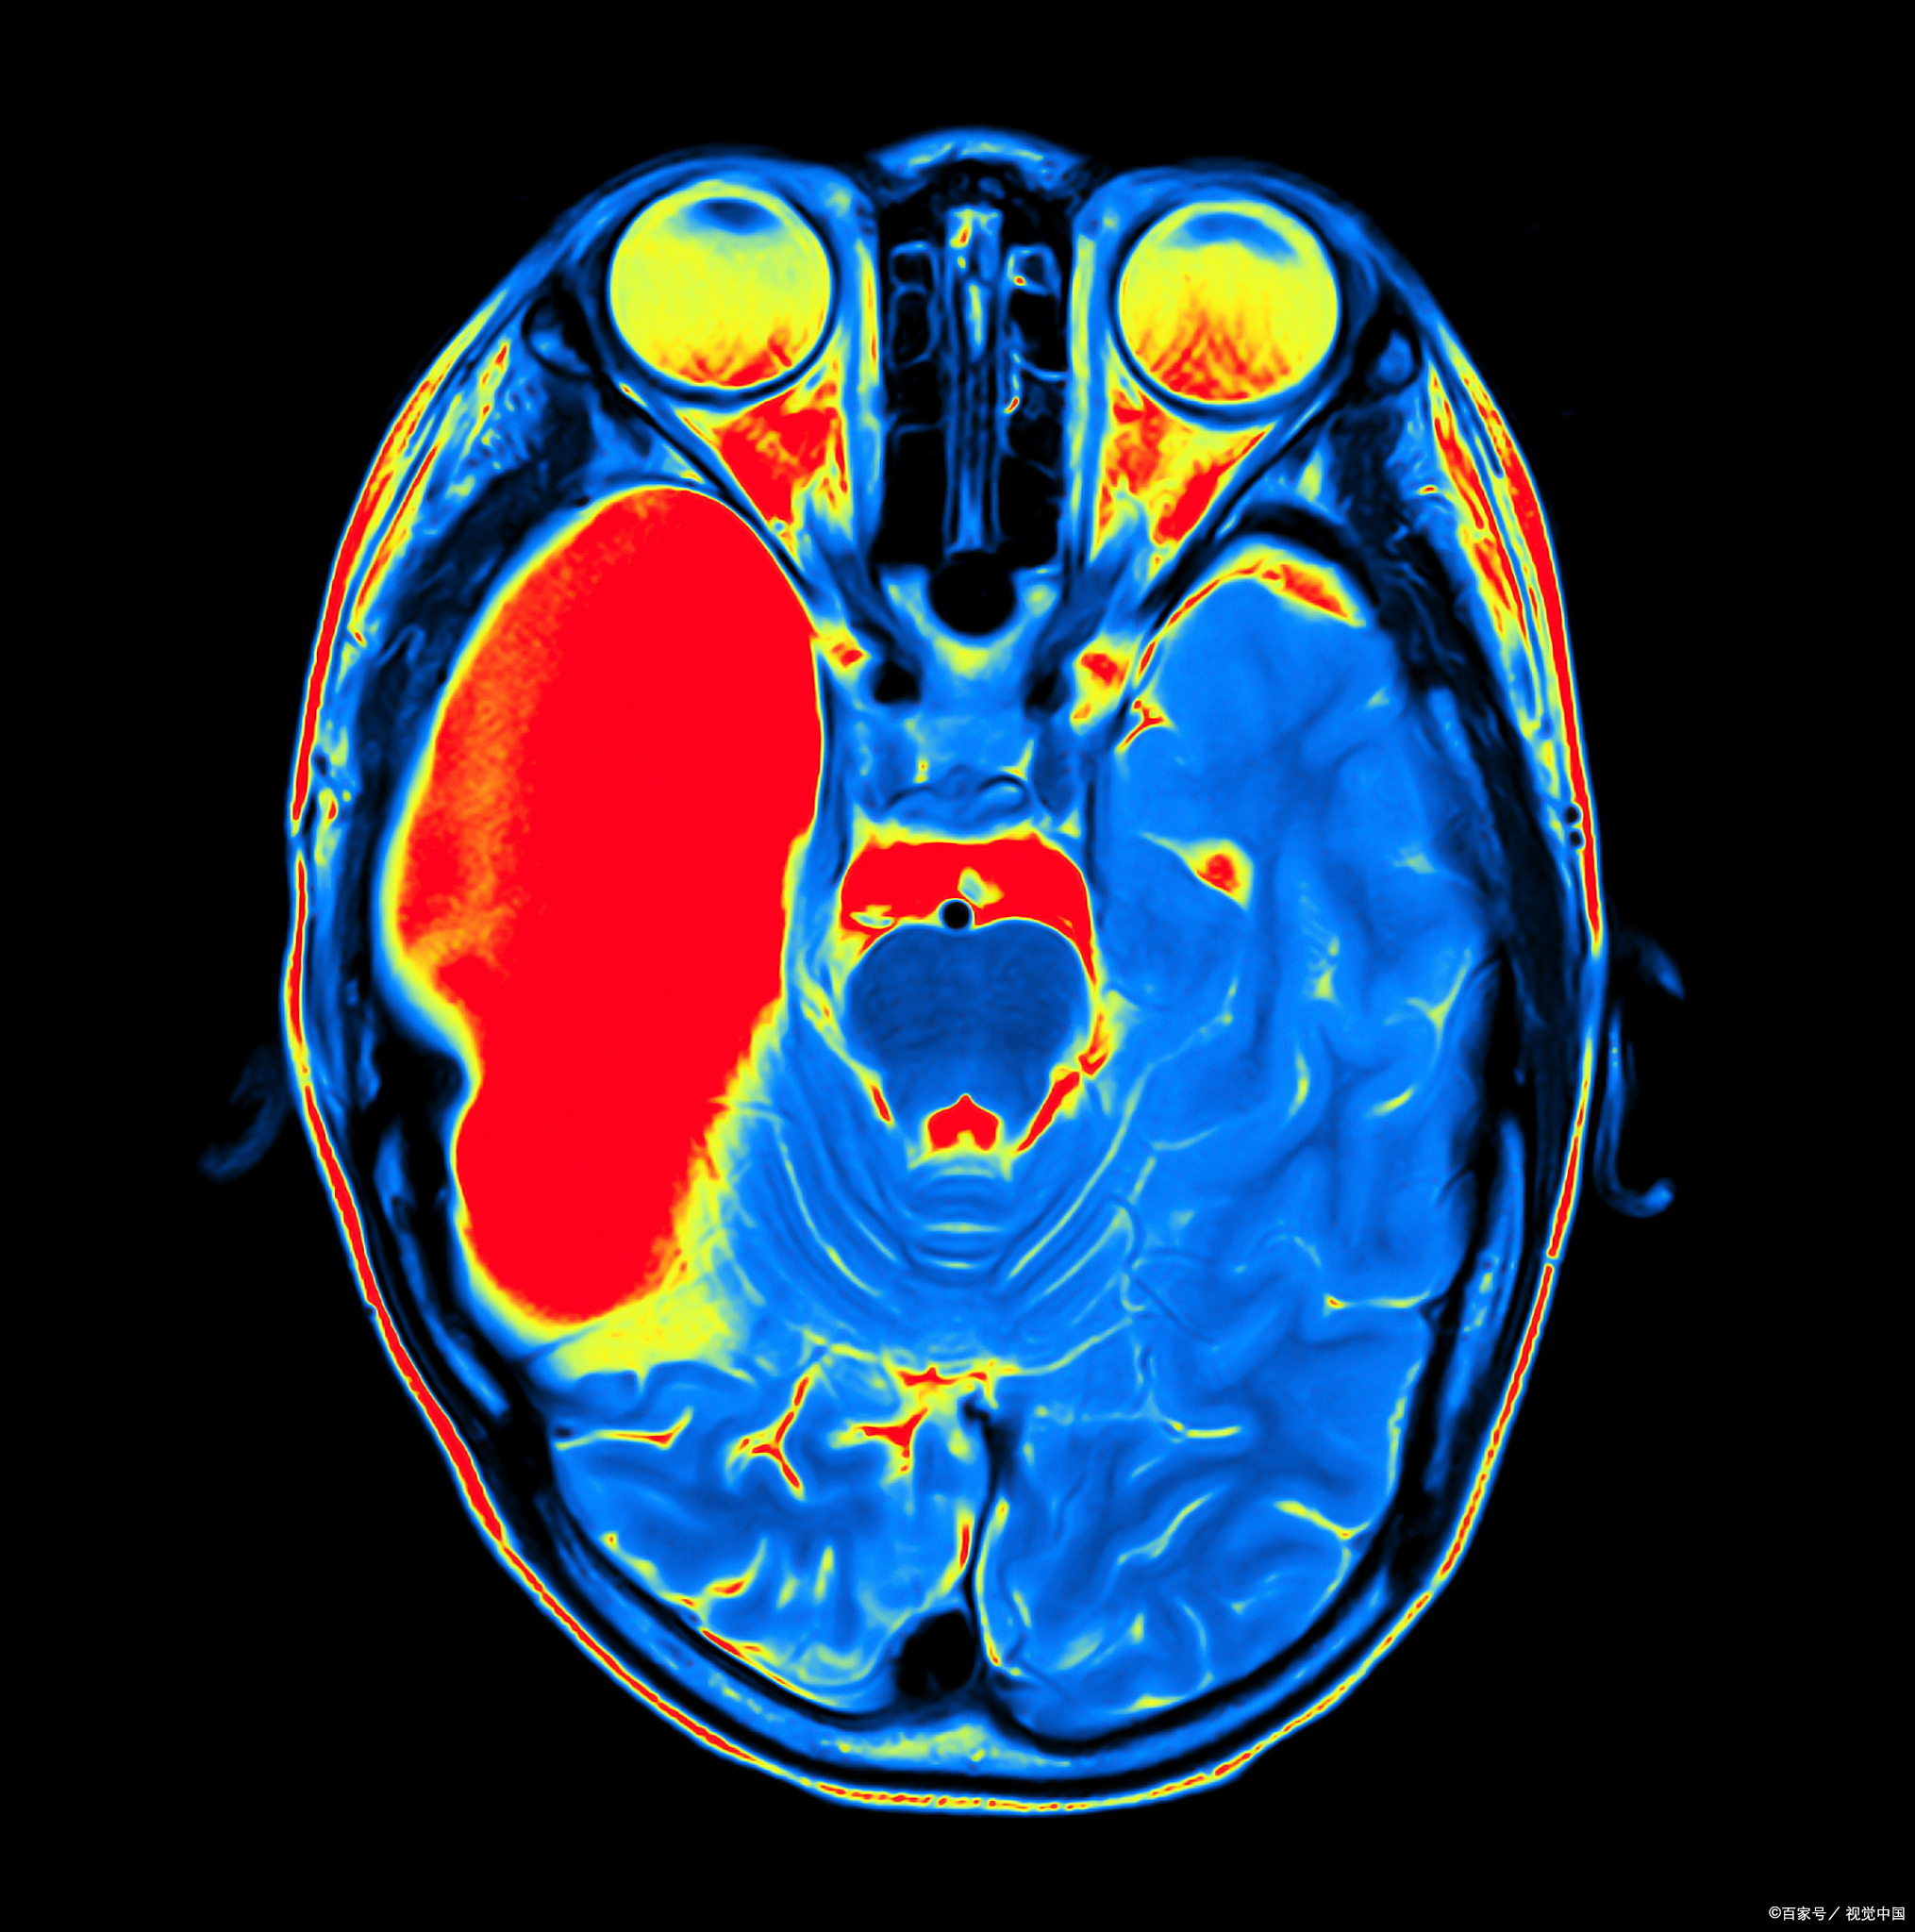

脑屏成像图片

在进行脑部ct检查时发现脑部高密度影.有患者怀疑是不是得脑肿瘤

可以通过成像技术观察和记录脑部结构和功能上的变化

世界上最强大的核磁共振成像仪首次捕捉到令人震惊的脑部扫描